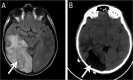

Figure 2A&B:

A: Magnetic resonance imaging (MRI) of the brain of a 12-year-old immunocompetent child six weeks after an initial resection of a right occipital fungal mass showing progression of the dense solid marginal tissue abnormality (arrow) and enhancement consistent with a granulomatous tissue abnormality. B: Brain MRI one month after the second resection showing partial resolution of the solid parenchymal abnormality (arrow).